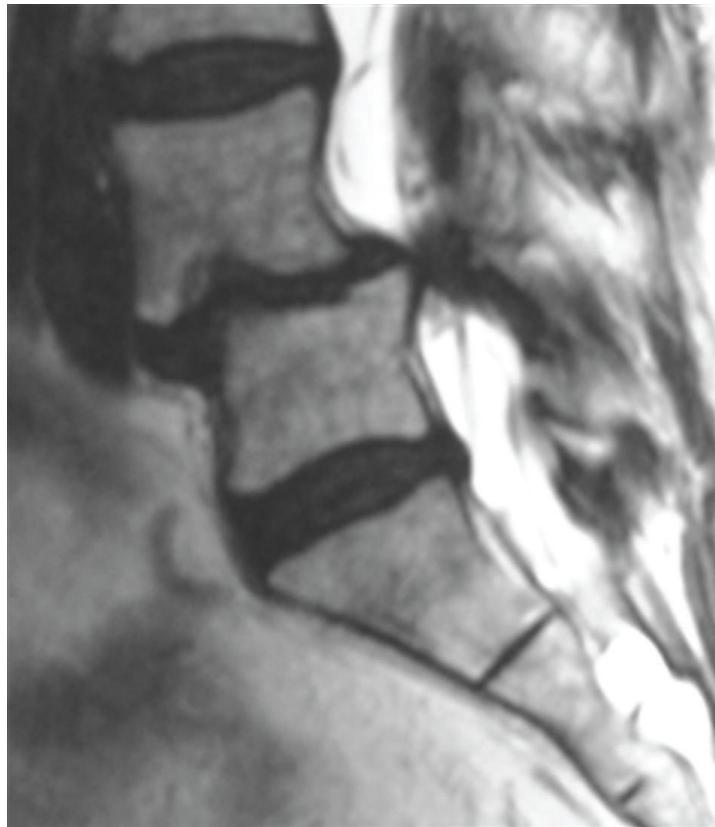

- Etiology: Severe compression of nerve roots in the thecal sac of lumbar spine, most commonly due to acute lumbar disc herniation

- Urgent MRI to confirm cause

- Prompt surgical decompression

- Should be performed within 24 hours, absolutely within 48 hours